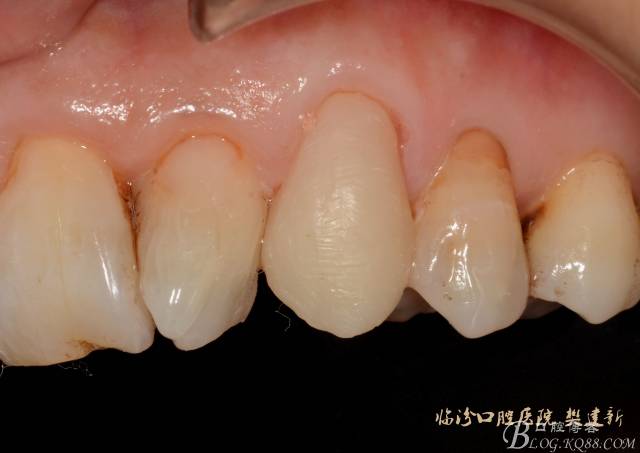

圖5  置纖維樁樹脂樁備牙后情況

640 (4).jpg